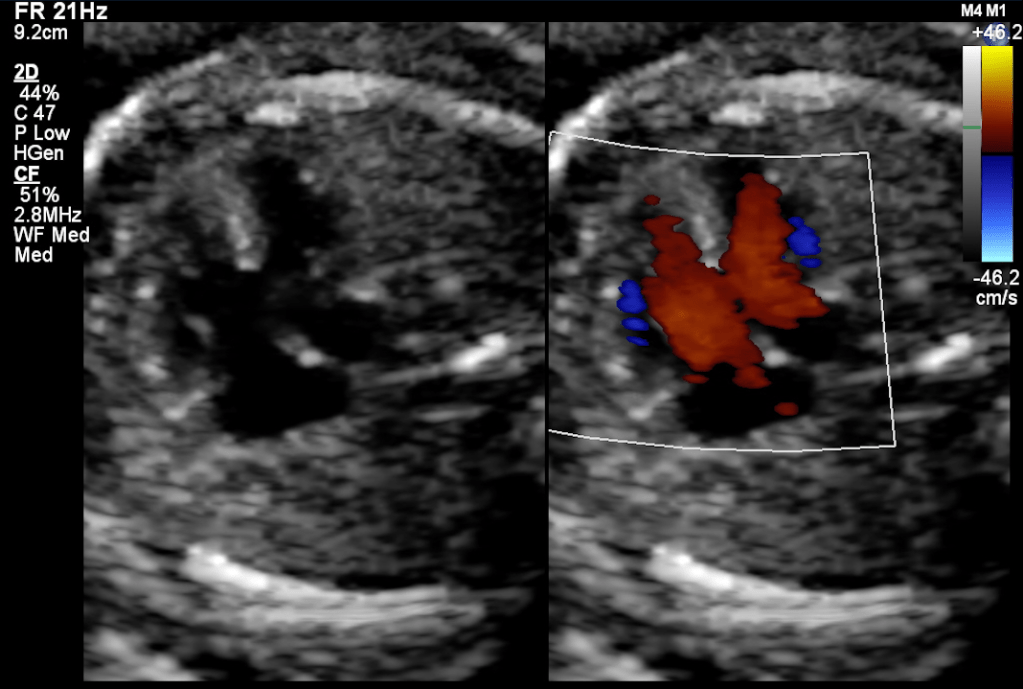

Smaller VSDs are much more common than a large defect. Also, the smaller defects are much more difficult to diagnose in early pregnancy fetal echocardiography because both the ventricle has similar pressures. Thus there is no significant color doppler flow can be seen across small VSD during most of the cardiac cycle. The 2D echo image also can miss a small VSD because of pixel spread of image due to significant magnification used during the echo.

The membranous defects pose a different kind of challenges to diagnoses by fetal echocardiography. This part of the septum is thin thus can appear as drop-out even in the absence of VSD there. Also, during color doppler, the color spill due to increase flow velocity of the outflow tract and great arteries crossover. Thus over-diagnosis is also common, and to avoid over-diagnosis, sometimes the diagnosis can be missed as well.

The presence of additional findings such as Tricuspid regurgitation (TR), Chambers / Arterial size discrepancy, along drop out at the septum might be an indicator of the presence of a ‘true VSD.’